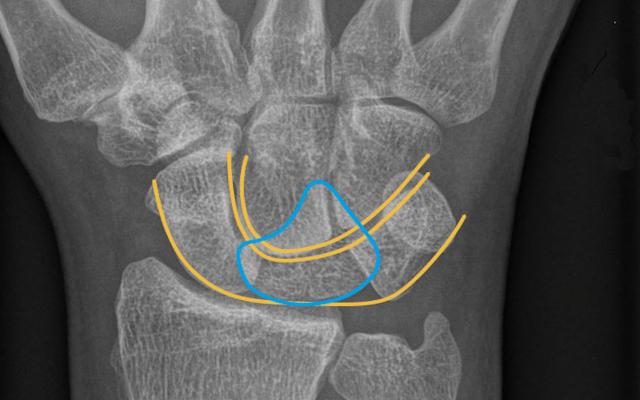

Een 67-jarige man kwam naar de Spoedeisende Hulp na een val op de uitgestrekte rechter pols, met pijnklachten en functiebeperking. Bij lichamelijk onderzoek viel een forse zwelling van de rechter hand en pols op met intacte sensibiliteit. Er was drukpijn ter hoogte van de tabatière anatomique en de dorsale zijde van de pols. Röntgenfoto’s lieten een perilunaire luxatie zien, dat wil zeggen dat de carpalia ten opzichte van het os lunatum naar dorsaal waren verplaatst en het os lunatum zelf niet verplaatst was ten opzichte van de as van de radius (figuur a). Op de anteroposterieure polsopname was tevens…